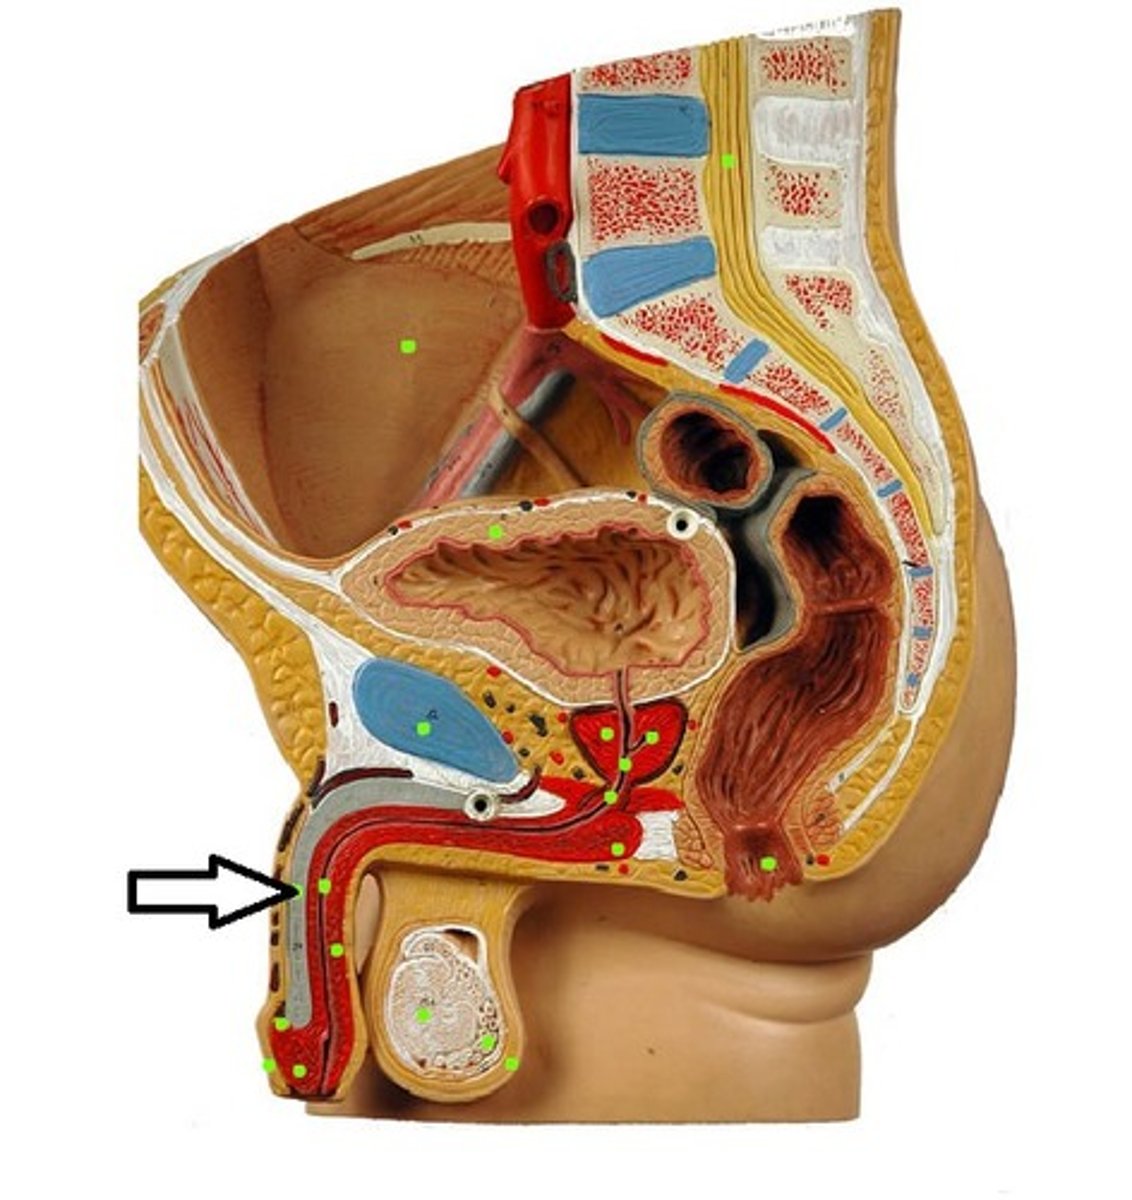

Penis

ampulla of vas deferens

ejaculatory duct

prostate gland

prostatic urethra

membranous urethra

epididymis

testes

scrotum

glans penis

corpora cavernosa

penile urethra

corpus cavernosum

corpus spongiosum

prepuce

bulbourethral gland

spermatic cord